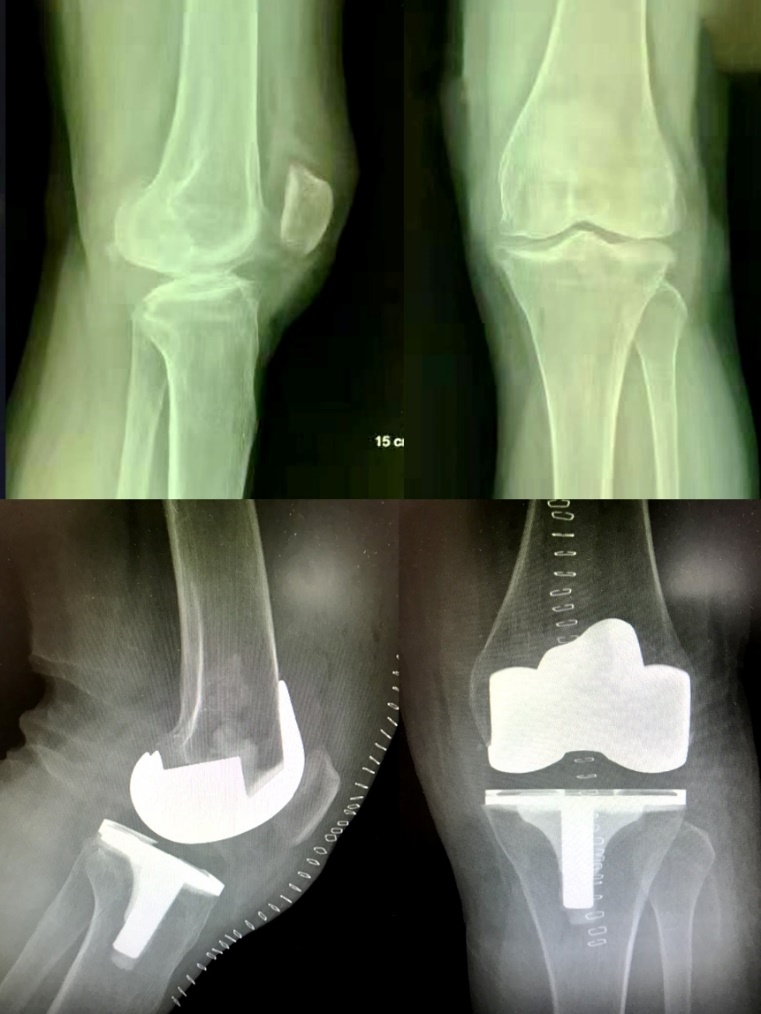

2019年8月13日和9月12日,由科室主任史占军教授主刀,为3位饱受膝关节炎病痛折磨的患者实施了全膝关节置换手术,术中首次使用了安择™膝关节,再次证明了施乐辉国产膝关节与一直以来提供的进口假体有着同样的品质。

史占军教授手术后对此款假体感受颇深,最大的改进在于前髁收窄设计,能够避免前髁的悬挂以及对周围软组织的刺激,它在假体和工具的设计上都给我们提供很好的帮助,这是南方医科大学南方医院的首款国产膝关节假体,相信它将是一个新的里程碑。

患者术前术后光片